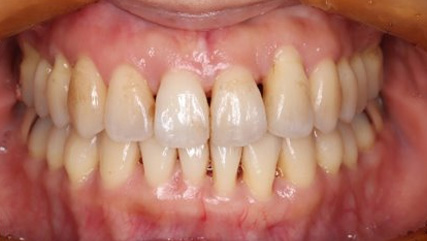

治療前

治療終了前